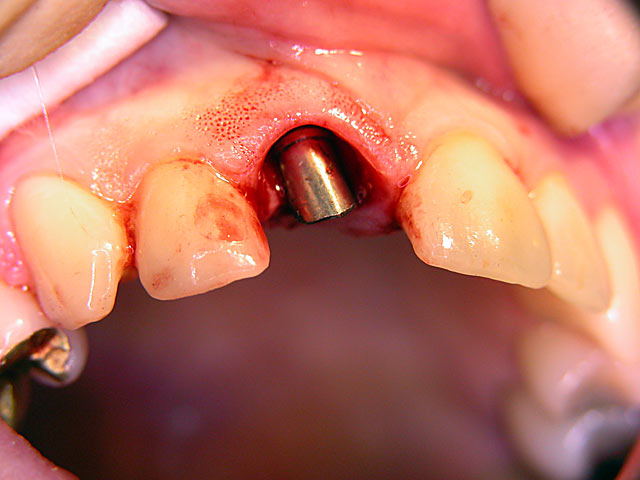

Sofort-Implantation: